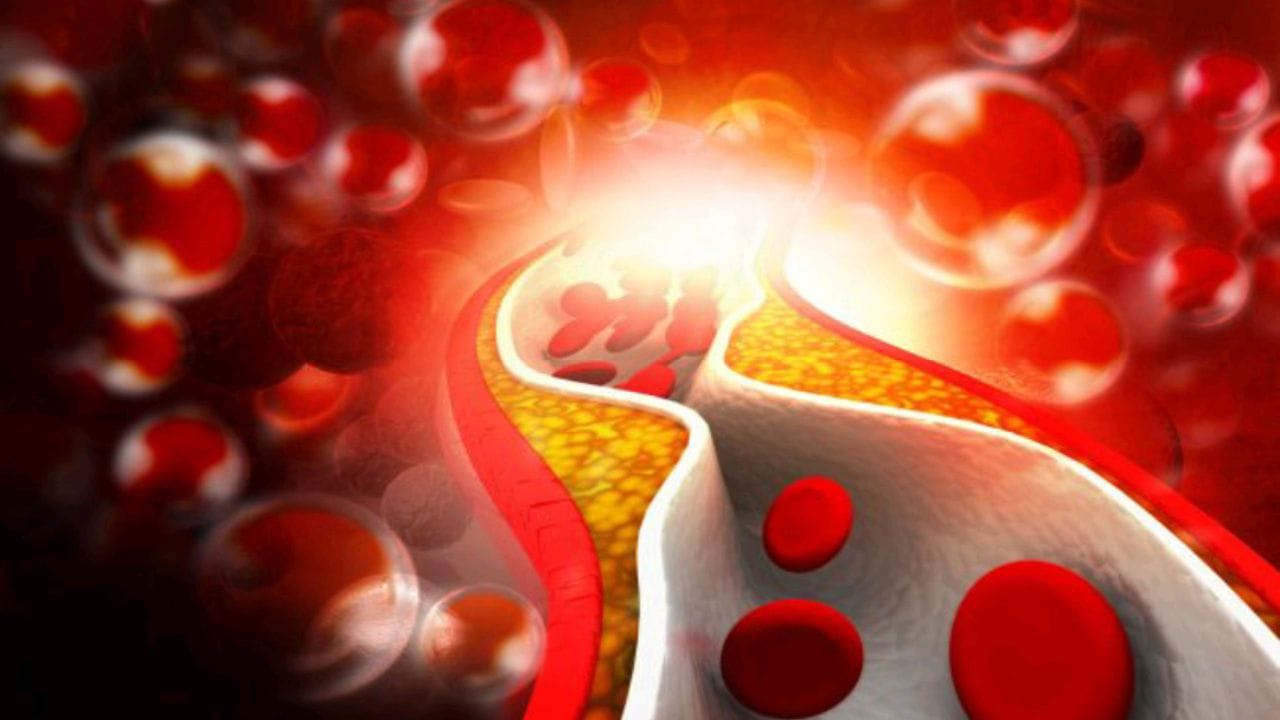

سعود الطبية توضح كيفية التحكم في كوليسترول الدم